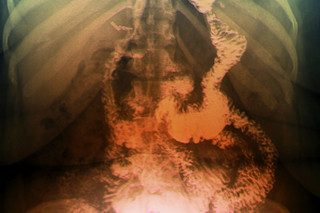

小肠的第一部分,也是最短的部分,长度不足一英尺,是十二指肠,它直接连接到胃。十二指肠将部分消化的食物与胆汁混合,胆汁是一种由肝脏产生的苦涩的黄绿色液体,有助于消化脂肪。食物从那里通过小肠八英尺长的中间部分——空肠,那里有指状突起吸收重要的糖类、氨基酸、维生素和小蛋白质。小肠的最后一段,回肠,分泌肠促胰素并吸收更多营养,然后排入大肠进行排泄。通过将这些肠道连接重新组合成新的配置,特谢拉可以深刻地重塑身体的化学成分。

现在在手术室里,在视频摄像头和高能灯的引导下,他站在南希·鲁比奥上方,通过五个“钥匙孔”进行手术——半英寸的切口,作为整洁、无血的入口。特谢拉用剪刀、缝合器和针线缝合,操纵着一对两英尺长的杆子,这些杆子是为肥胖患者设计的,因为他们的体型使得外科医生需要保持超过一臂的距离。肠道并不像教科书上整洁的线条图。它看起来像一堆松散的淡粉色香肠,上面覆盖着黄色布丁。在一个健康个体中,这层脂肪毯厚度不到八分之一英寸,呈蕾丝状,几乎透明。鲁比奥的肠道覆盖着一英寸厚的脂肪沉积,这使手术更加复杂。

特谢拉计划将鲁比奥的胃从一个拳头大小的袋子缩小成一个拇指大小的囊,大大限制她进食的量。他还打算将其重新连接到消化道更远下方的一段小肠。他抓住鲁比奥的胃,研究了一个大约两英寸宽的区域,“足以容纳四盎司食物”——大约半盒果汁的体积,不到其正常容量的十分之一。他剪开胃,胃的稠度像香蕉皮一样,将器官一分为二,然后将两侧缝合。他将迷你胃囊缝合到空肠,大约在十二指肠后面两英尺处。(旁路越长,吸收的营养越少,患者减掉的体重也越多。)然后特谢拉将悬挂在大胃囊上的肠道连接到小肠的最后一段,形成Y形连接,这便是该手术名称的由来。这使得胃中重要的消化液可以排入肠道。